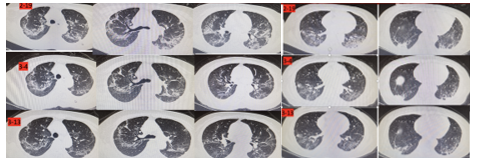

影像学检查( 2020年1月29日胸部CT )

经上述综合治疗,患者呼吸困难逐渐缓解,呼吸频率降至12-20次/分,应用鼻导管吸氧

2L/min 时指尖氧饱和度可达100%,感染指标恢复正常,炎症因子逐渐下降,凝血功能、心功能、电解质等恢复正常,复查胸部 CT

示双肺磨玻璃影、胸膜下斑片影较前吸收,且两次鼻咽拭子COVID-19核酸阴性,已达到新冠肺炎出院标准。

→ 患者胸部CT对比